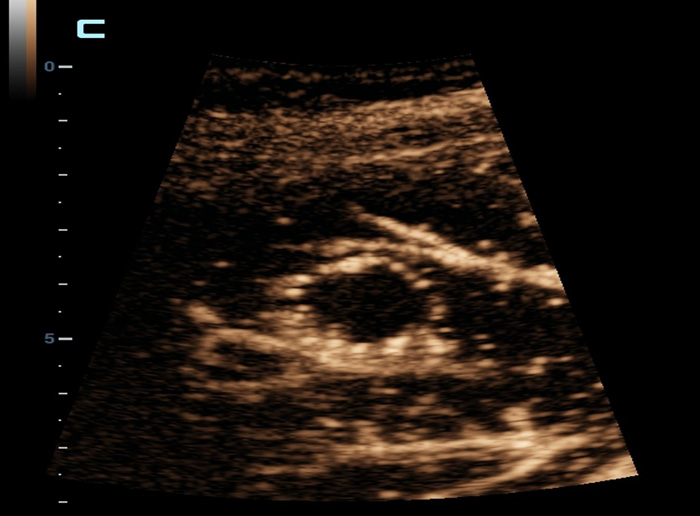

CEUS avan?ado

CEUS avan?ado

UWN+ (Ultra-Wideband Non-Linear) CEUS

CEUS ã Tumor maligno de mama

Ao utilizar tanto a segunda harm?nica quanto os sinais fundamentais n?o lineares, o UWN+ permite alta sensibilidade dos sinais das bolhas e maior dura??o de perfus?o com baixo MI, auxiliando nas avalia??es de tumores.

Avalia??o apû°s abla??o

Imagem de contraste UWN+

Detecta e utiliza os sinais fundamentais n?o lineares e os de segunda harm?nica, gerando imagens com melhorias significativas:

- Excelente sensibilidade do agente, mesmo com sinal fraco

- Tempo de perfus?o mais longo com menor IM

- Melhor visualiza??o da perfus?o de pequenos vasos com MFE (Micro Flow Enhancement)